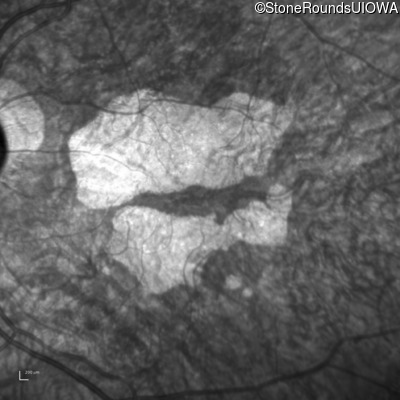

AR Stargardt Disease (IIA)

Age at visit: 69 years

This 69 year old man had excellent vision until 7 years ago when he first noticed some difficulty in dim light especially while driving.

AR Stargardt Disease ABCA4 Trp1101Stop TGG>TAG IVS30+1321 A>G AR